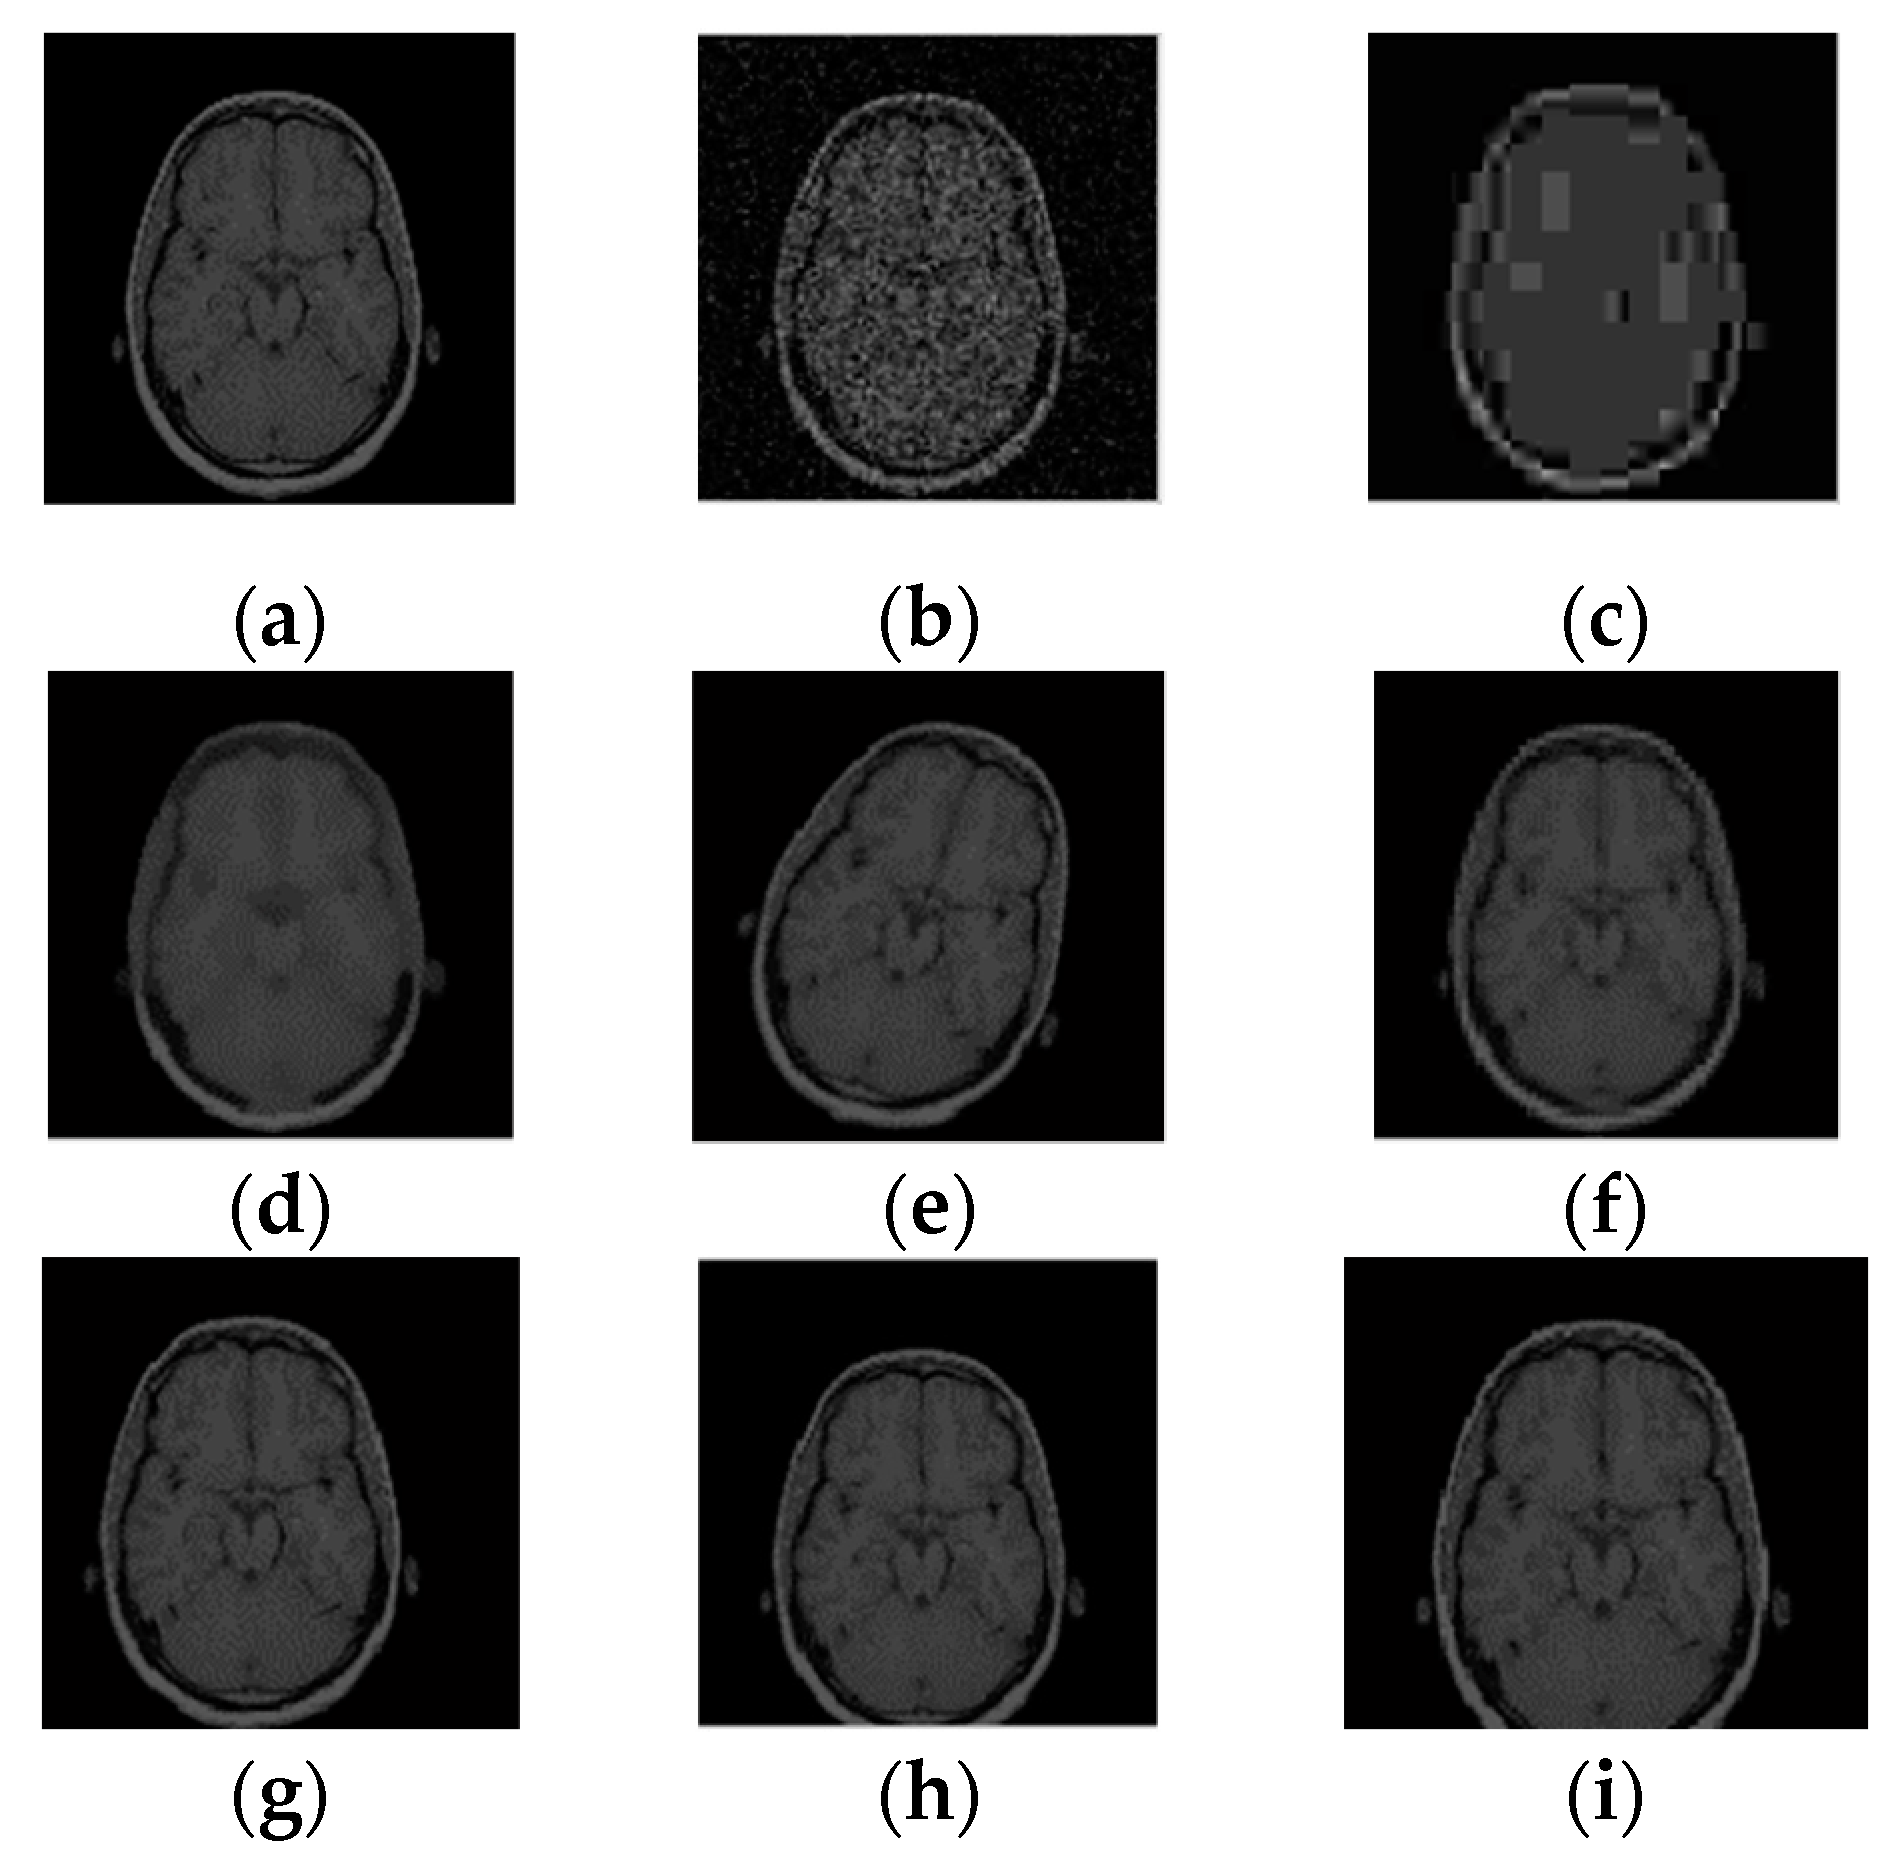

In order to find a visual feature applicable to medical images, a normal human brain image (128 pixels × 128 pixels) was randomly selected to carry out the DTCWT-DCT transformation, and this image was subjected to a variety of different types of attacks, as shown in Figure 7. By observing the coefficient data of the low-frequency part of the image after transformation, we found that although its numerical value changed significantly, its symbol remained basically the same. Table 1 lists the low frequency coefficients of the brain image under different attacks. In this paper, we selected 32 bits of low-frequency data for symbol transformation, and directly replaced data greater than or equal to 0 with 1, and all other data with 0. For the sake of explanation, we only list the first 10 data in the table; all data were in 1.0e+003 units. In this way, we obtained a set of DTCWT-DCT low-frequency coefficient symbol sequences of the original image, i.e., ‘1100010010’. As seen from Table 1, after transformation, the symbol sequences of all attacked images were consistent with the original image, and the NC values were all equal to 1.00.

Figure 7. Different attacks on the brain: (a) Original image; (b) Gaussian noise (1%); (c) JPEG compression (4%); (d) Median filter [3 × 3] (10 times); (e) Rotation (clockwise, 20°); (f) Scaling (×0.5); (g) Translation (5%, left); (h) Translation (7%, down); (i) Cropping (10%, Y direction).